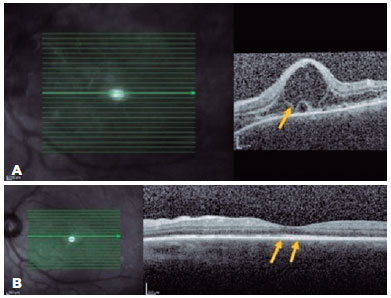

A 23-year-old woman presented with a sudden onset of reduced vision in her OD since the past 24 h, which was associated with headache and nausea. She had a history of bacterial keratitis in the OS caused by contact lens misuse that led to corneal thinning with three episodes of corneal perforation; the first two were successfully treated by cyanoacrylate glue, and the last one was complicated with persistent iris herniation. Subsequently, she underwent penetrating keratoplasty of the OS, 3 weeks before the OD event. Ophthalmic examination revealed a VA of 20/400 in the OD and counting fingers in the OS. Anterior-segment evaluation showed 3+ cells in the OD anterior chamber. Corneal edema restricted the evaluation of the anterior chamber and vitreous of the OS. Fundus examination revealed bilateral optic disc hyperemia and multifocal SRD. Ancillary tests were performed. FA showed bilateral diffuse early pinpoints and later pooling within the SRD. In addition, a remarkable optic disc hyperfluorescence was observed in the OD. Spectral-domain OCT revealed multifocal serous and bacillary retinal detachments and pigmented epithelial detachment (Figures 4A and 5A). A diagnosis of SO was made, and the patient was treated with high-dose systemic steroids (oral administration of prednisone 1.5 mg/kg/ day), intensive topical steroids, and topical atropine (1%). After 14 days of treatment, subretinal fluid improved in OU (Figures 4B and 5B). Oral prednisone dosage was gradually tapered, and 4 months after the onset, at a dosage of 0.45 mg/kg/day, the best-corrected VA values were 20/20 and 20/200 in the OD and OS, respectively. Eleven months after the onset of inflammation, the patient's condition was stable, without any oral or topical treatment. The sunset glow retinal changes remained without any evidence of inflammation recurrence.